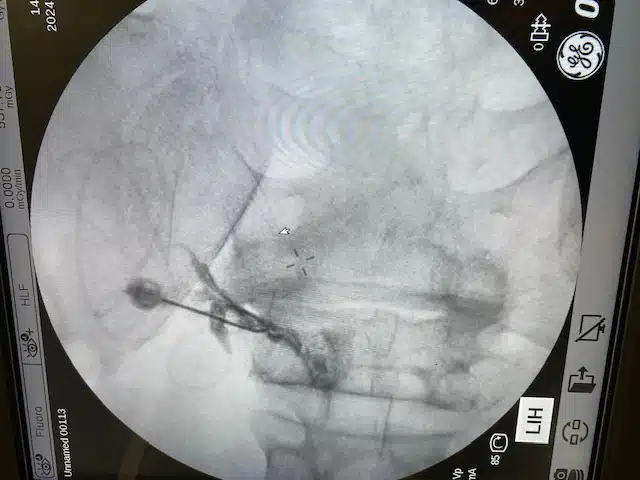

En selektiv nerverotsblokade innebærer at man går eksakt inn mot den aktuelle nerveroten og behandler denne med medikamenter. Det er en høyt spesialisert prosedyre som skal utføres av erfaren lege med høy kompetanse og riktig utstyr. Selektive nerverotsblokader utføres i røntgen gjennomlysning og med bruk av kontrast. Det må ikke forveksles med ultralyd-prosedyrer hvor det infiltreres medikamenter langs nervene perifert langt unna prolapset (perinevral infiltrasjon).

Strålesmerter kan være forårsaket av skiveutglidninger i ryggen (prolaps) som trykker mot nerven. Dette kalles isjias. Man kan også få utstrålende smerter av trange rotkanaler (spinal stenose) eller av en kjemisk irritasjon av nerven uten noe påviselig ytre trykk. Diagnosen stilles ut fra pasientens smertemønster og MR bilder. Det er obligatorisk med MR bilder før man vurderer intervensjonsterapi og disse bør være mindre enn 3 mnd gamle. Smerten brer seg belteformet til benet avhengig av hvilken skive som klemmer på nerveroten. Ut fra dette velger man det aktuelle nivå hvor blokaden skal settes. I røntgen gjennomlysning og ved hjelp av kontrastmiddel, plasseres nålen inn mot nerveroten.

Når man setter en selektiv nerverotsblokade (TFESI) går man inn med en nål i røntgen gjennomlysning som plasseres eksakt hvor nerven er i klem. Det settes en blanding av kortison og lokalbedøvelse. Lokalbedøvelsen kan gi en umiddelbar, men forbigående smertelindring noen timer. Den mer permanente effekten fra kortisonet kommer etter noen dager til uker. Kortison er et sterkt betennelsesdempende medikament og får hevelsen av nerveroten til å gå ned og trykket på nerven blir mindre. Kortisonet kan også få prolapset til å skrumpe. Man bedrer plassforholdene ved en kjemisk påvirkning og smerten reduseres. Som regel er det nødvendig å sette 2 nerverotsblokader med noen ukers mellomrom for å oppnå ideell synergieffekt. Man kan ofte unngå en operasjon etter en vellykket nerverotsblokade.